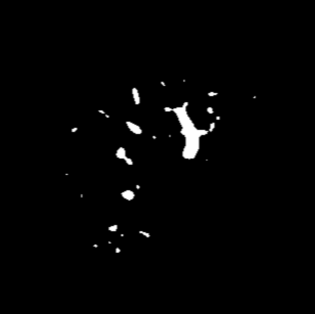

Manually segmenting the hepatic vessels from Computer Tomography (CT) is far more expertise-demanding and laborious than other structures due to the low-contrast and complex morphology of vessels, resulting in the extreme lack of high-quality labeled data. Without sufficient high-quality annotations, the usual data-driven learning-based approaches struggle with deficient training. On the other hand, directly introducing additional data with low-quality annotations may confuse the network, leading to undesirable performance degradation. To address this issue, we propose a novel mean-teacher-assisted confident learning framework to robustly exploit the noisy labeled data for the challenging hepatic vessel segmentation task. Specifically, with the adapted confident learning assisted by a third party, i.e., the weight-averaged teacher model, the noisy labels in the additional low-quality dataset can be transformed from "encumbrance" to "treasure" via progressive pixel-wise soft-correction, thus providing productive guidance. Extensive experiments using two public datasets demonstrate the superiority of the proposed framework as well as the effectiveness of each component.